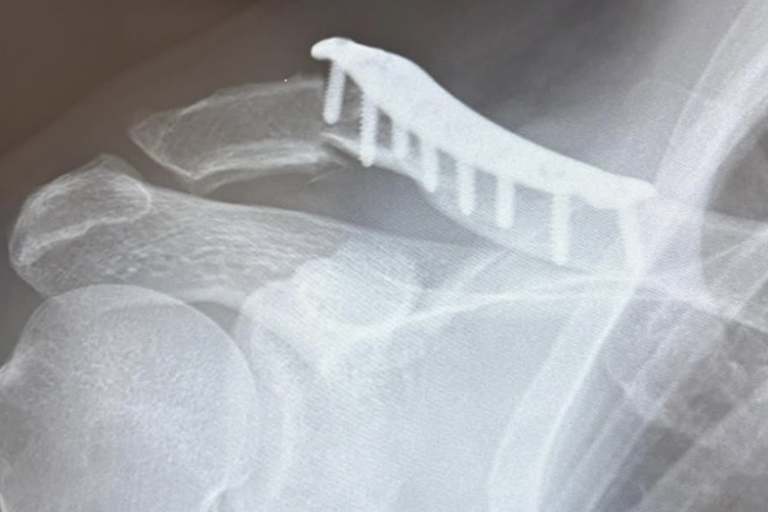

Für sein Heimrennen in Frauenfeld erhielt er die ärztliche Freigabe, beendete das Qualifikationsrennen auf Platz 8 und sicherte sich damit die ersten 3 WM-Punkte des Wochenendes. Den ersten Wertungslauf am Ostermontag beendete Valentin auf Platz 11 und im zweiten Rennen rangierte er sogar im Bereich der Top-5 als der heftige Abflug passierte, der ihn zur Aufgabe zwang. Es handelte sich übrigens um den gleichen Sprunghügel, der später auch Yamaha-Werksfahrer Maxime Renaux zum Verhängnis wurde. Beim Absprung wurde Guillod komplett ausgehebelt und landete am Ende des weiten Tables auf dem harten Untergrund. Guillod zog sich eine Schulterverletzung zu, die am vergangenen Mittwoch bereits operiert wurde. "Es wurde eine alte Platte entfernt und sie stabilisierten mein rechtes Schlüsselbein mit einer neuen Platte", erklärte der Schweizer. "Ich werde die nächsten 2 WM-Läufe verpassen. Voraussichtlich werde ich am 24. Mai in Ernée wieder am Start stehen." Nach der Pechsträhne von 2 Grands Prix fiel Guillod auf Tabellenplatz 17 zurück.